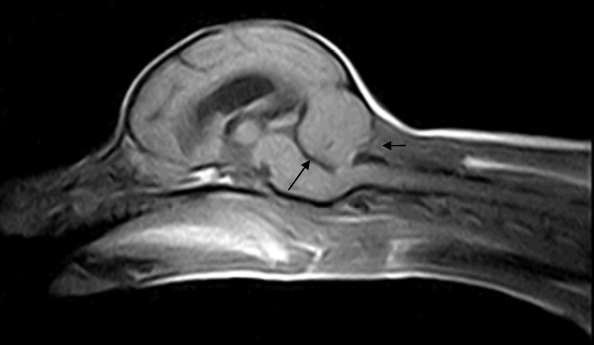

| T1 | T2 |

|---|---|

![]() | ![]() |

| infartion์ด ์๊ธด ํ์ ๋ถ๋ถ (=wedge shape) ํธ์ธก์ฑ์ผ๋ก ์กด์ฌ | infarction์ด ๋ฐ์ํ ๋ถ์๊ฐ ๊ฒ๊ฒ ๊ด์ฐฐ๋จ. |

์ค๋ฅธ์ชฝ(์ฌ์ง์ ์ผ์ชฝ) ๋ถ์์ ๊ตญ์์ ์ธ infarction โ ischemic necrosis๊ฐ ๋ฐ์ํ๊ณ ์์. โ embolism์ด ์ ์ ์ฆ์์ ์์ธ.